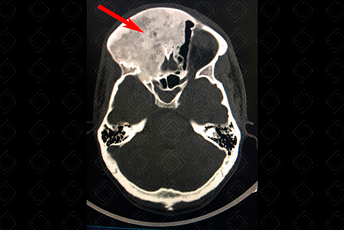

Texto alternativo para a imagem Figuras 1 e 2. Créditos: Dra. Elazir Mota - Rio de Janeiro/RJ

Descrição das figuras 1 e 2: Tomografia computadorizada de crânio evidenciando lesão expansiva, predominantemente hiperdensa, com aspecto em vidro fosco, na região frontal direita estendendo-se às células etmoidais e cavidade nasal bilateralmente (seta vermelha).

• Tomografia computadorizada: Característica da lesão, vemos que ela apresenta a clássica apresentação em “vidro fosco” ou “vidro despolido”. Esse aspecto de imagem deve nos fazer pensar na possibilidade de displasia fibrosa e sugerir seu diagnóstico (figuras acima);